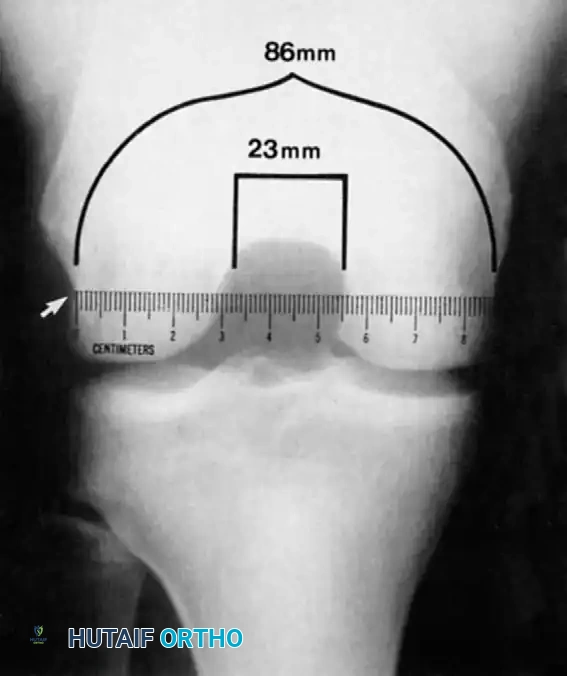

Notch Width Index:

Souryal and Freeman identified intercondylar notch stenosis as a significant risk factor for noncontact ACL tears. The Notch Width Index is the ratio of the width of the intercondylar notch to the width of the distal femur at the level of the popliteal groove.

Image

Fig. 43-103 Notch width index is ratio of width of intercondylar notch to width of distal femur at level of popliteal groove (arrow). Ruler must be parallel to joint line. Narrowest portion of notch at level of ruler is to be measured.